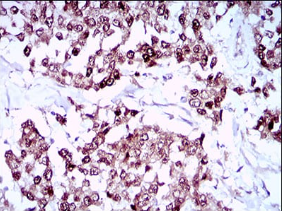

SOX10 Mouse Monoclonal antibody[2E7E8]

IHC    1/200 - 1/1000